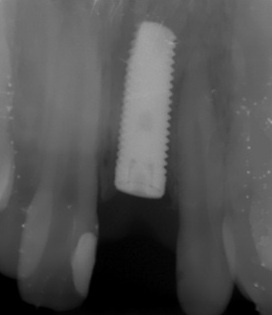

The surgery of an implant opening without a vestibule-oral graft throwing away was carried out in six months after the surgical stage. Availability of a sufficient amount of soft tissues in the region of implant placement made it possible to give up the usage of zirconium abutments and make use of a standard anatomic abutment to obtain positive clinical result.

The permanent metal-ceramic crown was manufactured later on.

Complete restoration of aesthetic look and function (Photo 9 and 10).